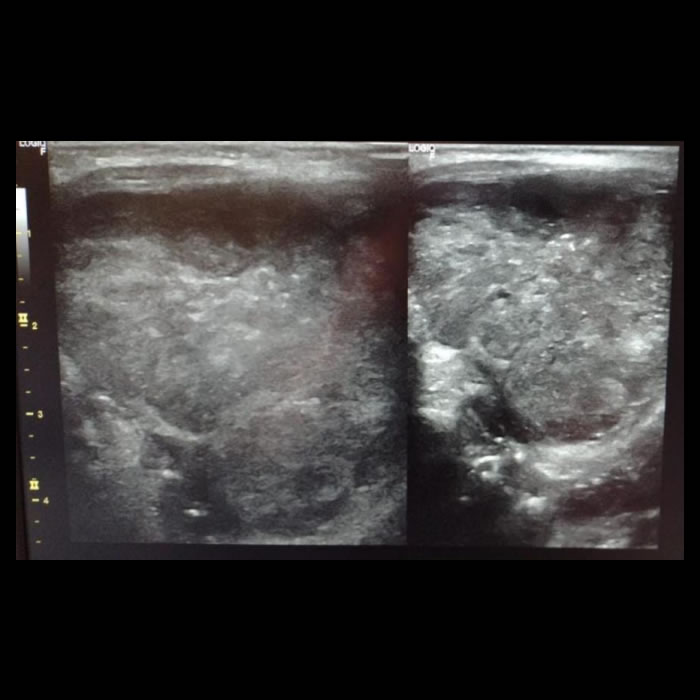

Niña de dos años sin App de relevancia que consulto en varias oportunidades en diferentes centros de salud por odinofagia. Presenta la siguiente lesión en piso de la boca.